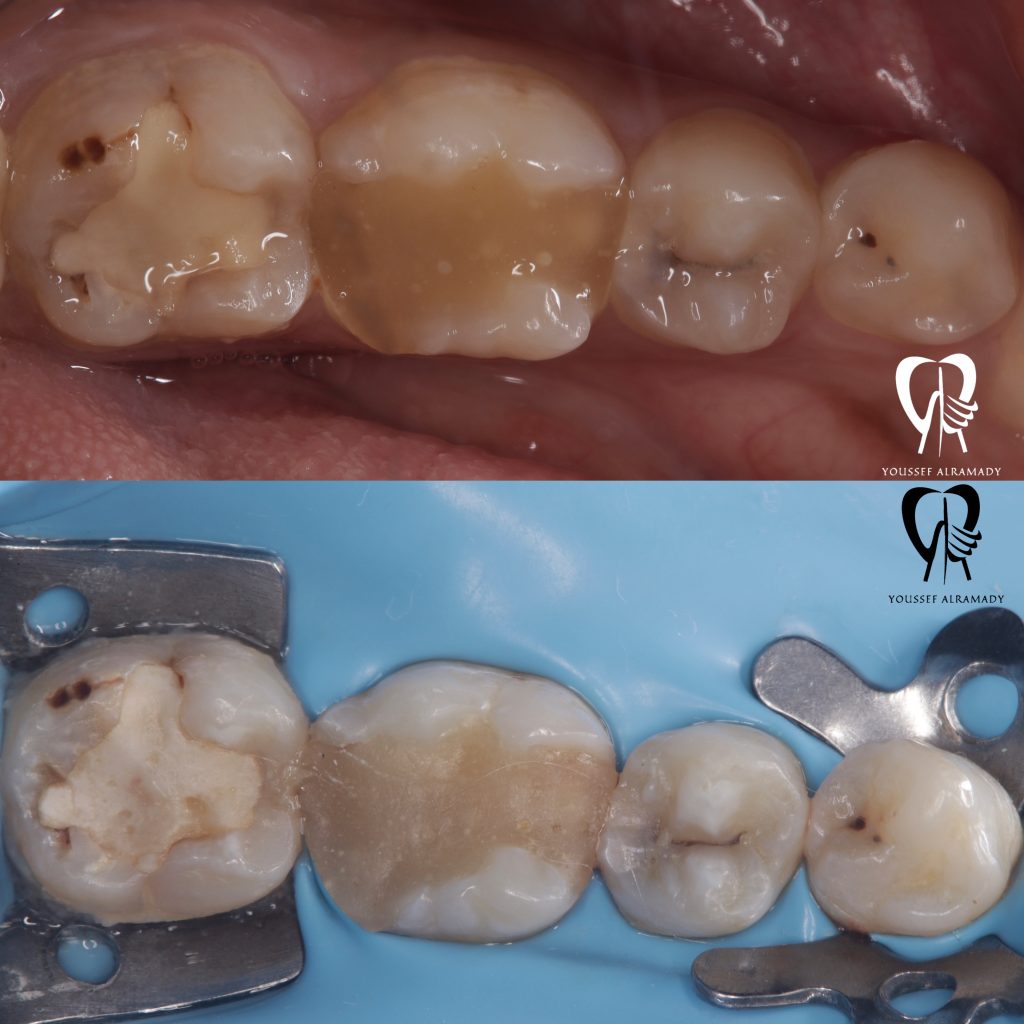

1st visit :- (left side)

1- Defective restoration & caries removal

2- IDS + RC then placement of ever x posterior to increase fracture resistance

3- Partial overlay prep for tooth no.36 / occlusal veneer perp for tooth no.37

2nd visit:- (right side)

Same steps were applied to the right side